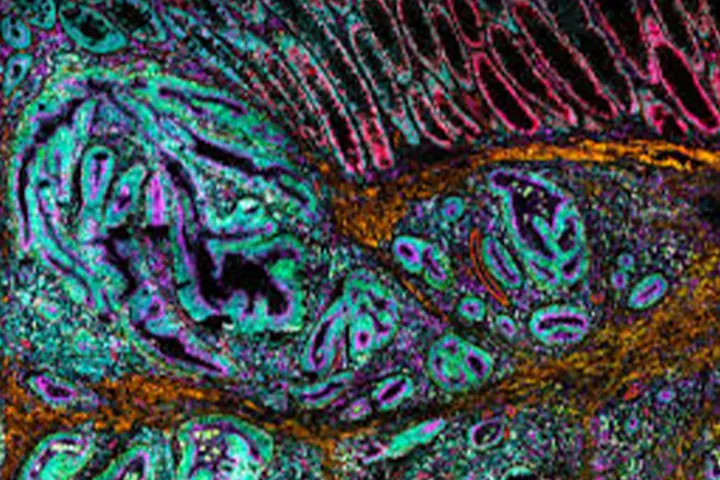

Seminar highlight: Introducing the MACSima™ System for high-parameter spatial biology

The MACSima platform offers fully automated ultra-high-content imaging based on cyclic immunofluorescence, enabling researchers to analyze hundreds of markers within a single tissue section or cell sample without damaging the specimen. This approach provides precise spatial insight into cell localization and interactions within complex tissue environments.